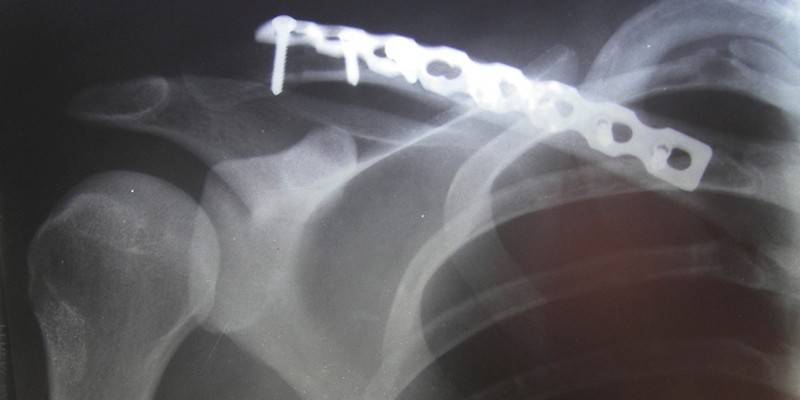

Chirurgia

Mocowanie za pomocą metalowych igieł |

Niski koszt. |

Rozerwane więzadło przegubowe zewnętrznego fragmentu obojczyka często się nie regeneruje. |

Śruba mocująca |

Niezawodność mocowania. |

Może powodować dysfunkcję kończyny górnej. |

Więzadło plastikowe (lawsanoplastyka) |

Uważa się za najbardziej skuteczną operację, jeśli pacjent ma zwichnięcie obojczyka z pęknięciem więzadeł. |

Nie oznaczone |

Mocowanie przycisku |

Odzyskiwanie jest szybsze niż instalowanie szprych lub śrub. |

Uraz obojczyka może się powtórzyć. Blizny pozostają w miejscu szycia guzików. |